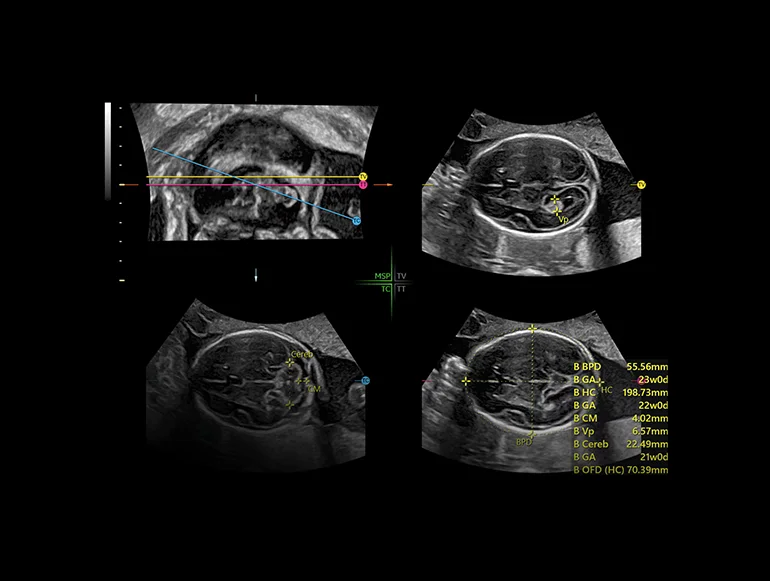

SonoCNS

SonoCNS на основе ИИ выравнивает и отображает рекомендуемые проекции и результаты измерений при объемной 3D-визуализации мозга плода, тем самым поддерживая выполнение последовательных измерений и высокую эффективность.